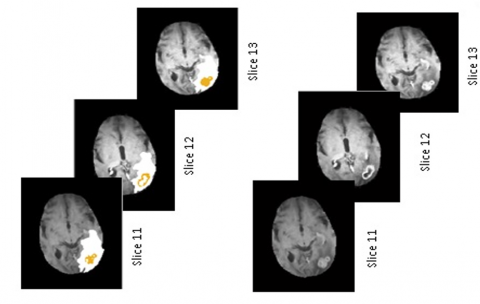

The segmentation outcomes derived from the proposed framework are defined as follows: First, the ICM algorithm is launched to perform segmentation of the Flair image into three regions: edema, background, and other tissues. The contour of the edema mask was then overlaid on the T1-w image to highlight the edema region. Figure 3 displays the results of applying ICM segmentation to three consecutive slices of the first patient’s case image. The outputs are the segmented edema region, edema mask “Maskedema” and the outlined T1-w image “imgT1-w”.

Figure 3. Edema segmentation by ICM algorithm: (a) Flair image; (b) Edema mask; (c) Edema mask outlined on T1-w image